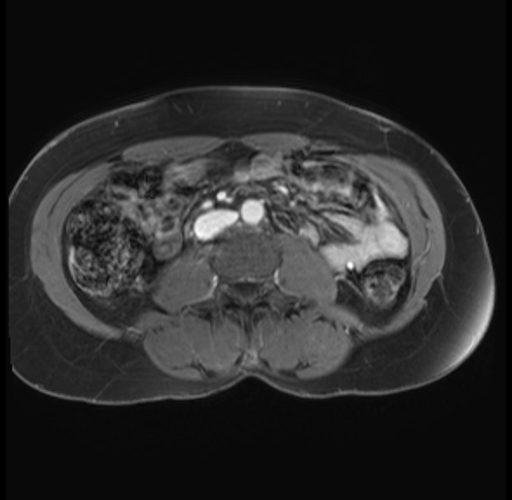

Imaging Analysis

Look through the patient's CT scan to identify any areas of concern for the necessary procedure.

Based on your CT findings, which issue(s) are present and would give reason for "planned slowing down moment(s)" in this case?

Considering a standard distal pancreatectomy procedure, what step(s) of the operation would you do differently in this case?